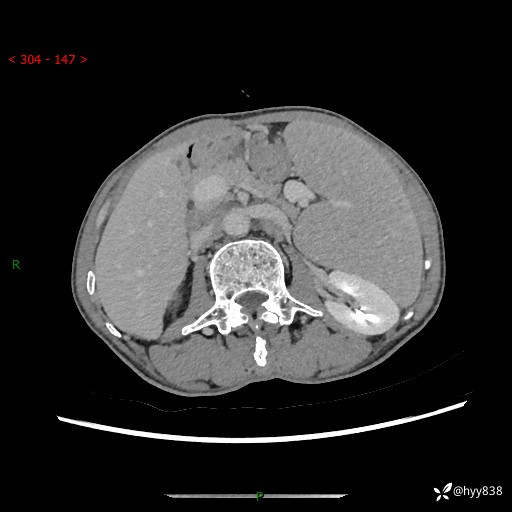

老年男性,脾大并脾脏弥漫粟粒状低密度,淋巴瘤 VS 肉芽肿 VS 血管瘤---结果公布

简要病史: 患者于3月前无明显诱因出现脾大,伴腹部轻微不适,具体不详,无腹痛、腹泻、腹胀,无头晕、头痛、乏力,无恶心、呕吐、呕血,无胸闷、气短、胸痛不适

上腹部CT平扫+增强